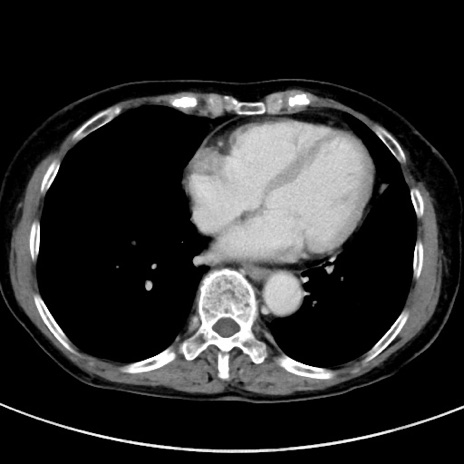

症例23(横断像)

【症例】70歳代女性

【主訴】下腹部痛・嘔吐

【現病歴】2日前より腹痛あり。昨日嘔吐あり。症状改善しないため来院。

【既往歴】胃GISTに対して胃部分切除後。

【身体所見】BT 37.1℃、BP 128/77mmHg、腹部:平坦・軟、下腹部に圧痛あり。

【データ】WBC 10200、CRP 0.31